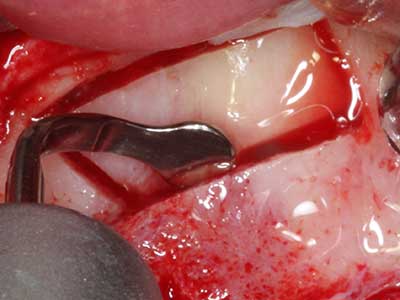

When surgical procedures are performed on bone in the immediate vicinity of sensitive structures such as blood vessels or nerves, rotary instruments pose a significant risk of iatrogenic injury. Piezoelectric devices can be helpful for preparation of bone covers and removal of hard tissue close to nerves, particularly for exposure of nerves after iatrogenic injury but also during nerve lateralization for resective and reconstructive procedures or implant placement (Fig. 17-20). Light contact between the piezotip and the nerve does not generally result in damage but proceeding incautiously with saw-like motions or attachments where a residual bone substrate remains may cause temporary or even permanent nerve damage. However, the risk of damage is considered to be substantially lower than when using saws or milling instruments (Pereira, Gealh et al. 2014).

Fig. 18: Preparation of a cortical cover with the piezo bone saw (Piezomed, W&H).

Fig. 19: Surgical site after neurolysis and removal of osteoma.

Fig. 20: The removed bone cover is re-adapted and fixed with an osteosynthesis screw (KLS Martin, Tuttlingen).